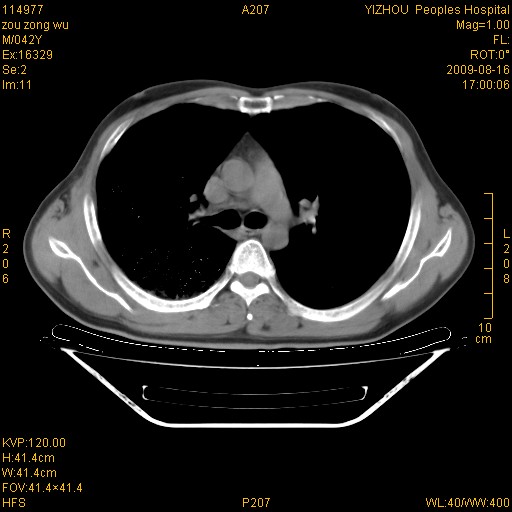

以下是引用zjzjr在2009-8-17 10:42:00的发言:[br]右侧间质性肺炎伴纤维化,右肺下叶肺囊肿伴感染(不除外外伤后引起),右肺野及胸壁软组织\\肝内见多发斑点状,中枪了吧.右侧胸膜肥厚\\粘连.